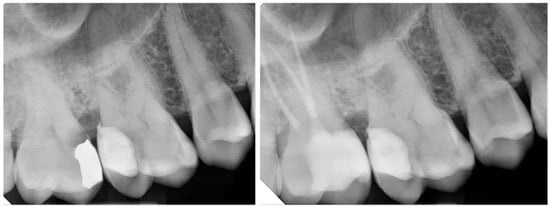

- Aziz, A.M.; Suliman, S.; Sulaiman, T.A.; Abdulmajeed, A. Clinical and Radiographical Evaluation of CAD-CAM Crowns with and without Deep Margin Elevation: 10-Year Results. J. Prosthet. Dent. 2024, in press. [Google Scholar] [CrossRef]

| 4. Aziz et al., 2024 [52] | Long-term clinical & radiographic study | DME under CAD/CAM ceramic crowns | Clinical and radiographic evaluation over 10 years | CAD-CAM crowns with vs. without DME | DME is a viable long-term option for subgingival margins in full crowns |